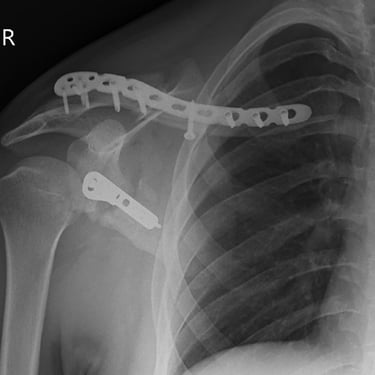

Limb reconstruction and complex trauma surgery

Trauma (Fractures)

Orthopedic trauma (fractures) refers to injuries to the musculoskeletal system, like bones, joints, and muscles, often from accidents, falls, or sports